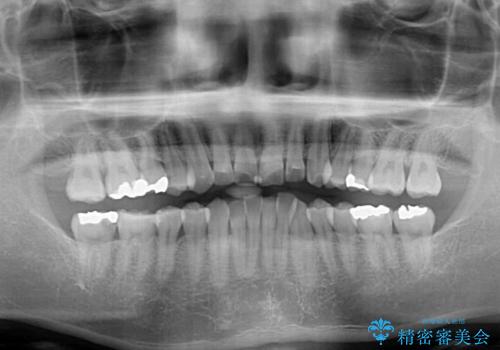

- 右下奥歯の虫歯がしみて痛いとのことで来院された患者様です。

神経近くにまで及ぶ大きな虫歯でしたが、速やかに処置を行い、痛みは即日解消されました。

虫歯が大きかったため、クラウンによる補綴治療が必要になる旨をお伝えしたところ、矯正治療にも興味があるとのことでした。

短期間で手間のかからない方法がご希望でしたので、ワイヤー装置による矯正治療を行うこととし、矯正治療後に右奥2歯をセラミッククラウンにて補綴することとしました。